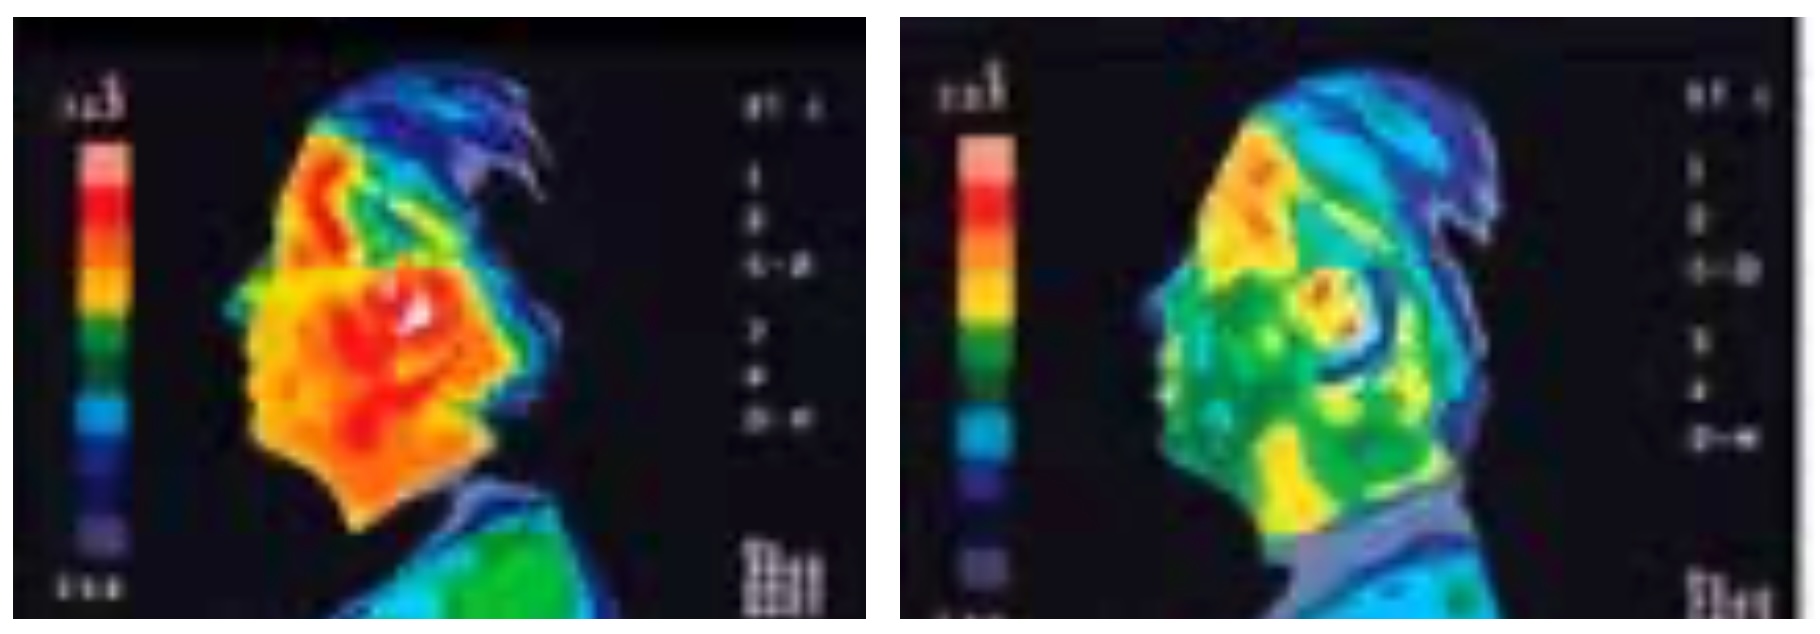

- Etude d'observation : moins d'échauffement localisé au niveau du crâne durant un appel. Si votre téléphone portable n'est pas protégé et que vous le gardez près de votre oreille, la température des cellules cérébrales peut augmenter localement jusqu'à 2°C. Il a été prouvé en laboratoire que, avec HSC sur le téléphone portable, l'échauffement des cellules cérébrales ne se produit pas ou très peu (à droite).